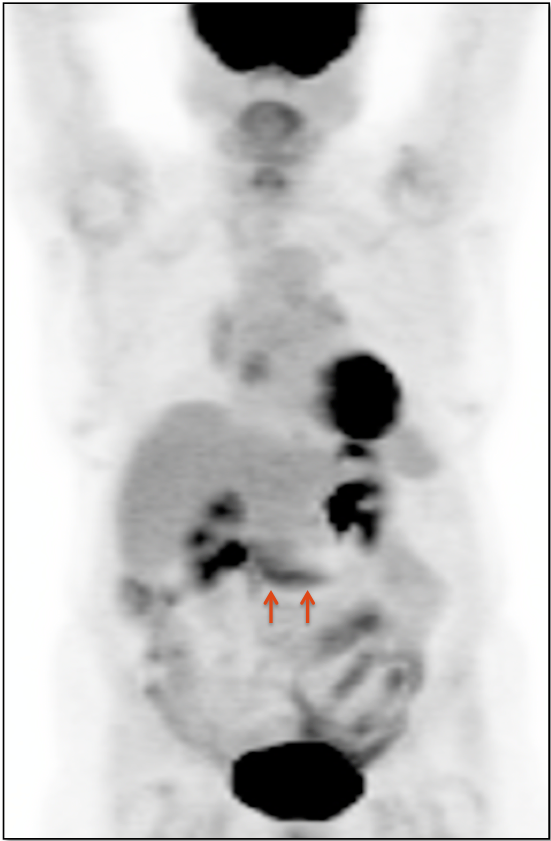

4. Abdomen & Pelvis

- Peritoneal Carcinomatosis

- Distant Disease: Most commonly to the liver, peritoneum, lung and bone.